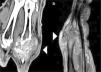

An 80 year-old male patient with a history of controlled high blood pressure, presented with a lesion in the dorsal region at the base of his third finger of the right hand, of several months duration. Physical examination of the lesion revealed that it was of solid consistency and partially deep layer attached. It was therefore diagnosed as a soft tissue tumor. An ultrasound scan was requested which detected a soft tissue mass with diffuse echotexture (Fig. 1A). In view of these findings, CT and MR scans were performed. From these tests we observed that the tumor had a lobulated morphology, contained calcifications and eroded the adjacent bony surfaces (Figs. 1B and 2). The tumor enhanced heterogeneously following the administration of intravenous line contrast dye. As a result of these findings, we decided to perform a biopsy in which uric acid crystals were detected, confirming the diagnosis of arthropathy by crystal deposits (Fig. 3).